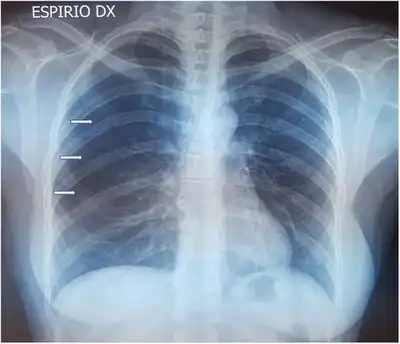

| Pneumothorax shown on a chest x-ray. Air fills the space between the collapsed left lung and the chest wall. | |